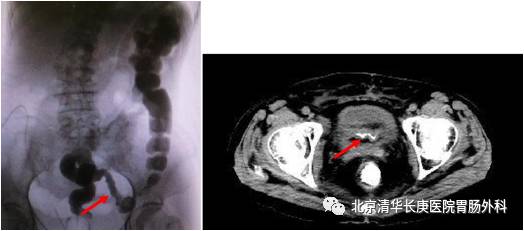

对于结直肠和小肠的狭窄部位的确定是手术主要解决的问题,因此通过造影和 CT可以综合准确判定。

或者受损伤肠管与髂血管、输尿管等重要脏器、血管粘连固定也为手术风险提前预警做了精准的术前评估,可以在术前进行输尿管支撑管的放置预防副损伤。